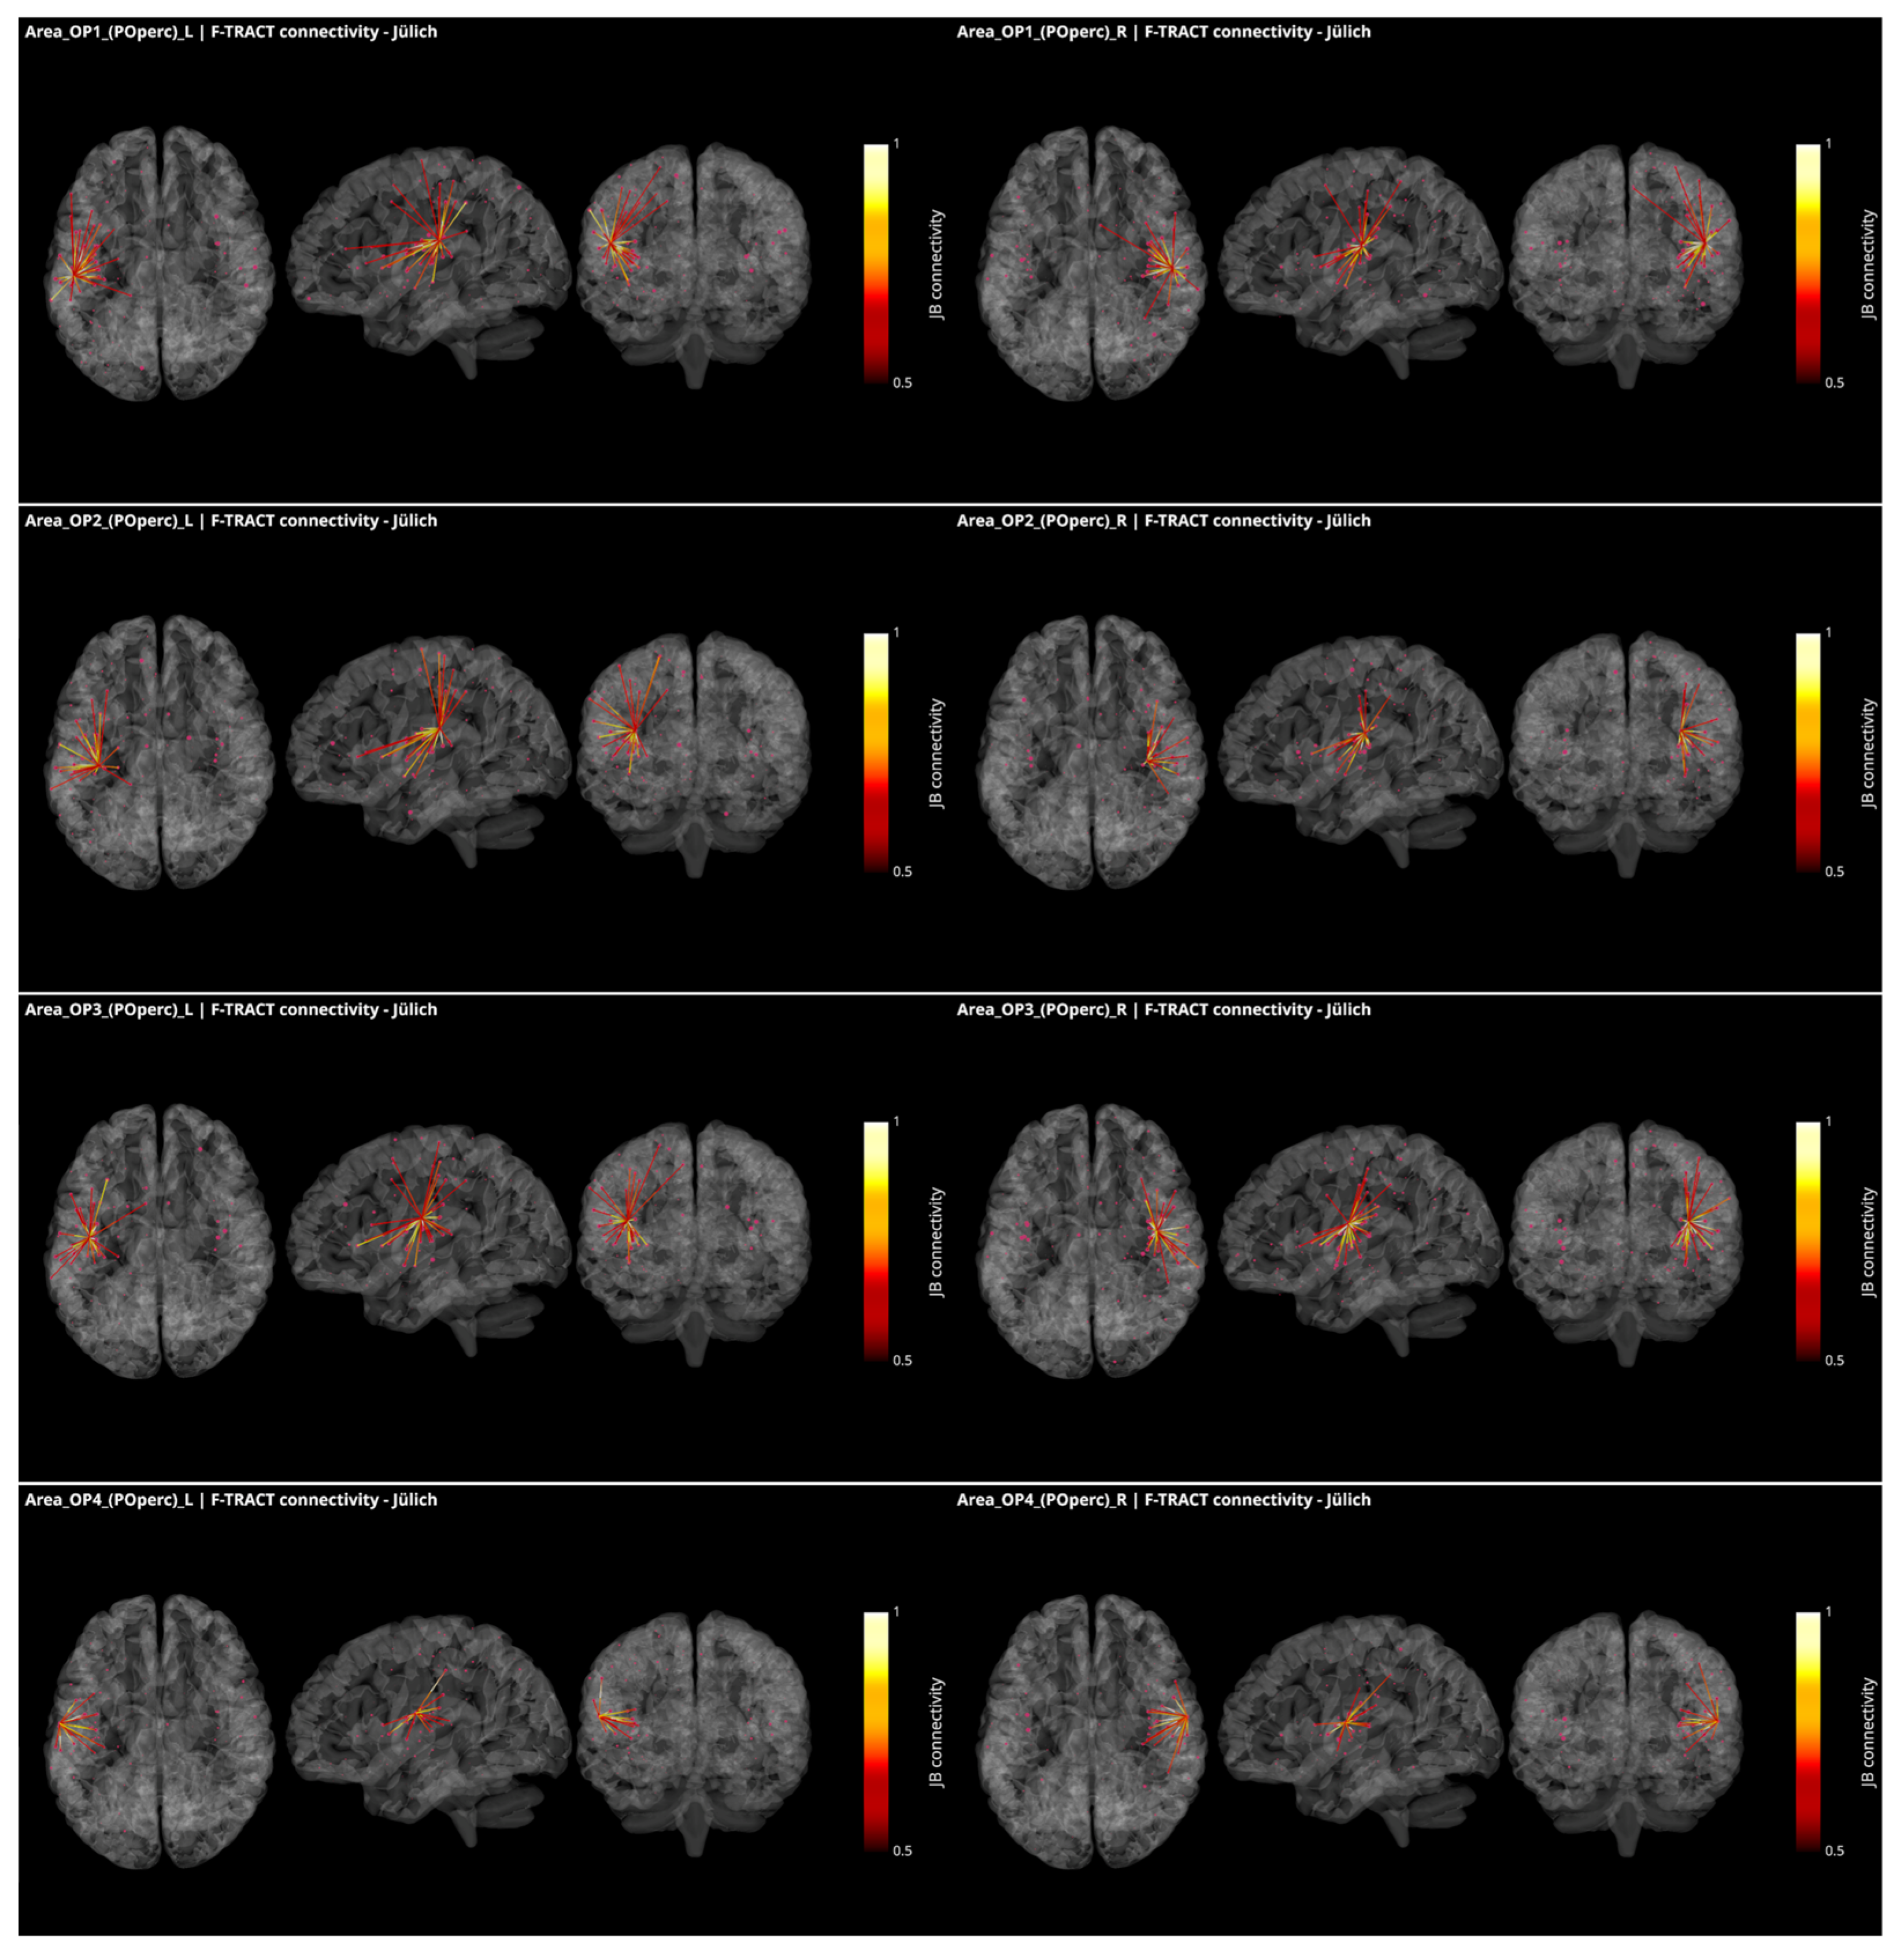

3.3. Operculo–Insular Connectivity

4.2. Functional and Structural Connectivity of the Parietal Operculum and Insular Cortex

- Trebaul, L.; Deman, P.; Tuyisenge, V.; Jedynak, M.; Hugues, E.; Rudrauf, D.; Bhattacharjee, M.; Tadel, F.; Chanteloup-Foret, B.; Saubat, C.; et al. Probabilistic functional tractography of the human cortex revisited. Neuroimage 2018, 181, 414–429. [Google Scholar] [CrossRef]

- Lemaréchal, J.-D.; Jedynak, M.; Trebaul, L.; Boyer, A.; Tadel, F.; Bhattacharjee, M.; Deman, P.; Tuyisenge, V.; Ayoubian, L.; Hugues, E.; et al. A brain atlas of axonal and synaptic delays based on modelling of cortico-cortical evoked potentials. Brain J. Neurol. 2021, awab362. [Google Scholar] [CrossRef]

- Eickhoff, S.B.; Jbabdi, S.; Caspers, S.; Laird, A.R.; Fox, P.T.; Zilles, K.; Behrens, T.E. Anatomical and functional connectivity of cytoarchitectonic areas within the human parietal operculum. J. Neurosci. 2010, 30, 6409–6421. [Google Scholar] [CrossRef]